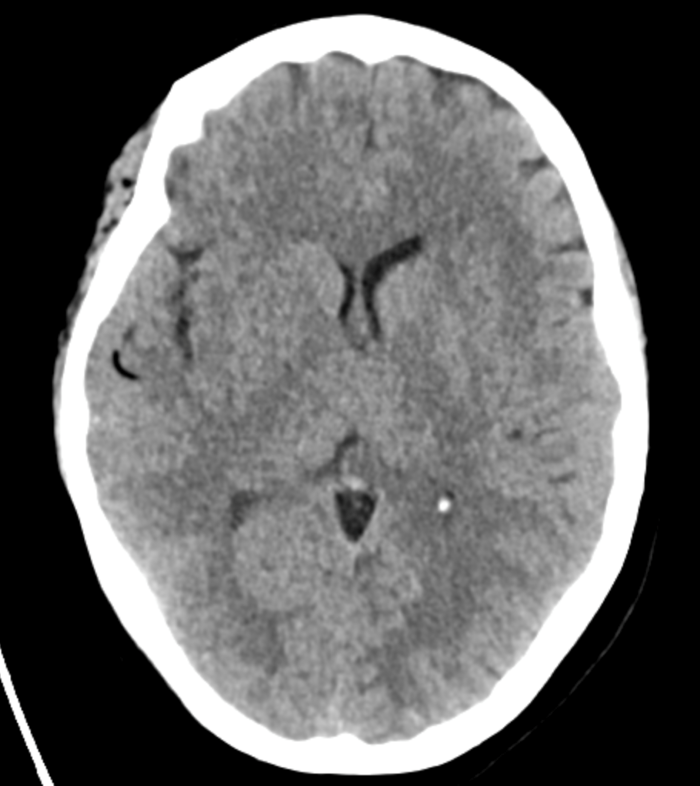

Initial objective data included T 37C, HR 85, RR 20, BP 153/109, spO2 98%. Glucose 102. Basic labs obtained and were unremarkable. Patient was rapidly taken to CT for stroke imaging. No contraindications to thrombolytics were identified. At 1708, noncontrast head CT showed no hemorrhage, but an abnormal hypodensity along the right middle cerebral artery concerning for an air embolus was visualized. CT angiogram head and neck was also suggestive of air embolus and CT perfusion brain demonstrated 27 mL of critical hypoperfusion at the right posterior middle cerebral artery distribution.

Figure 1: Non contrast Head CT showing air in the R MCA distribution